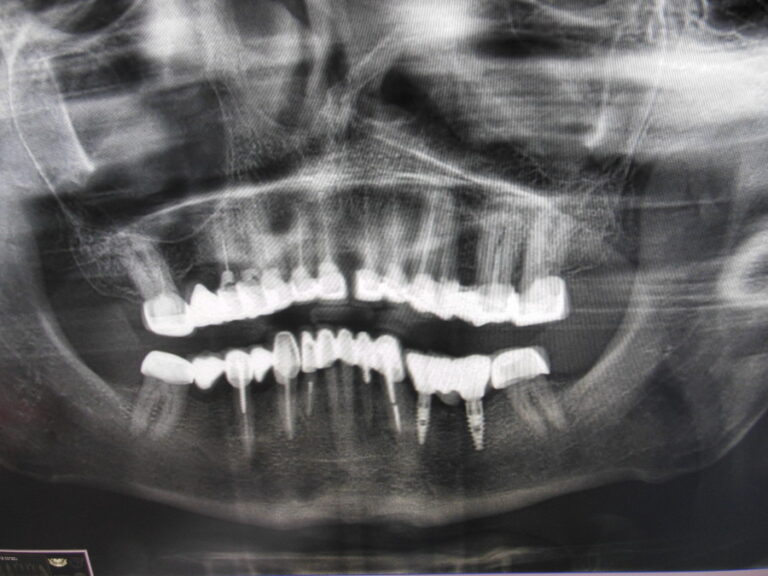

Implanty zygomatyczne

Przykłady implantologii

Zastosowanie implantoprotetyki w przypadku gdy klasyczna protetyka nie sprawdza się.